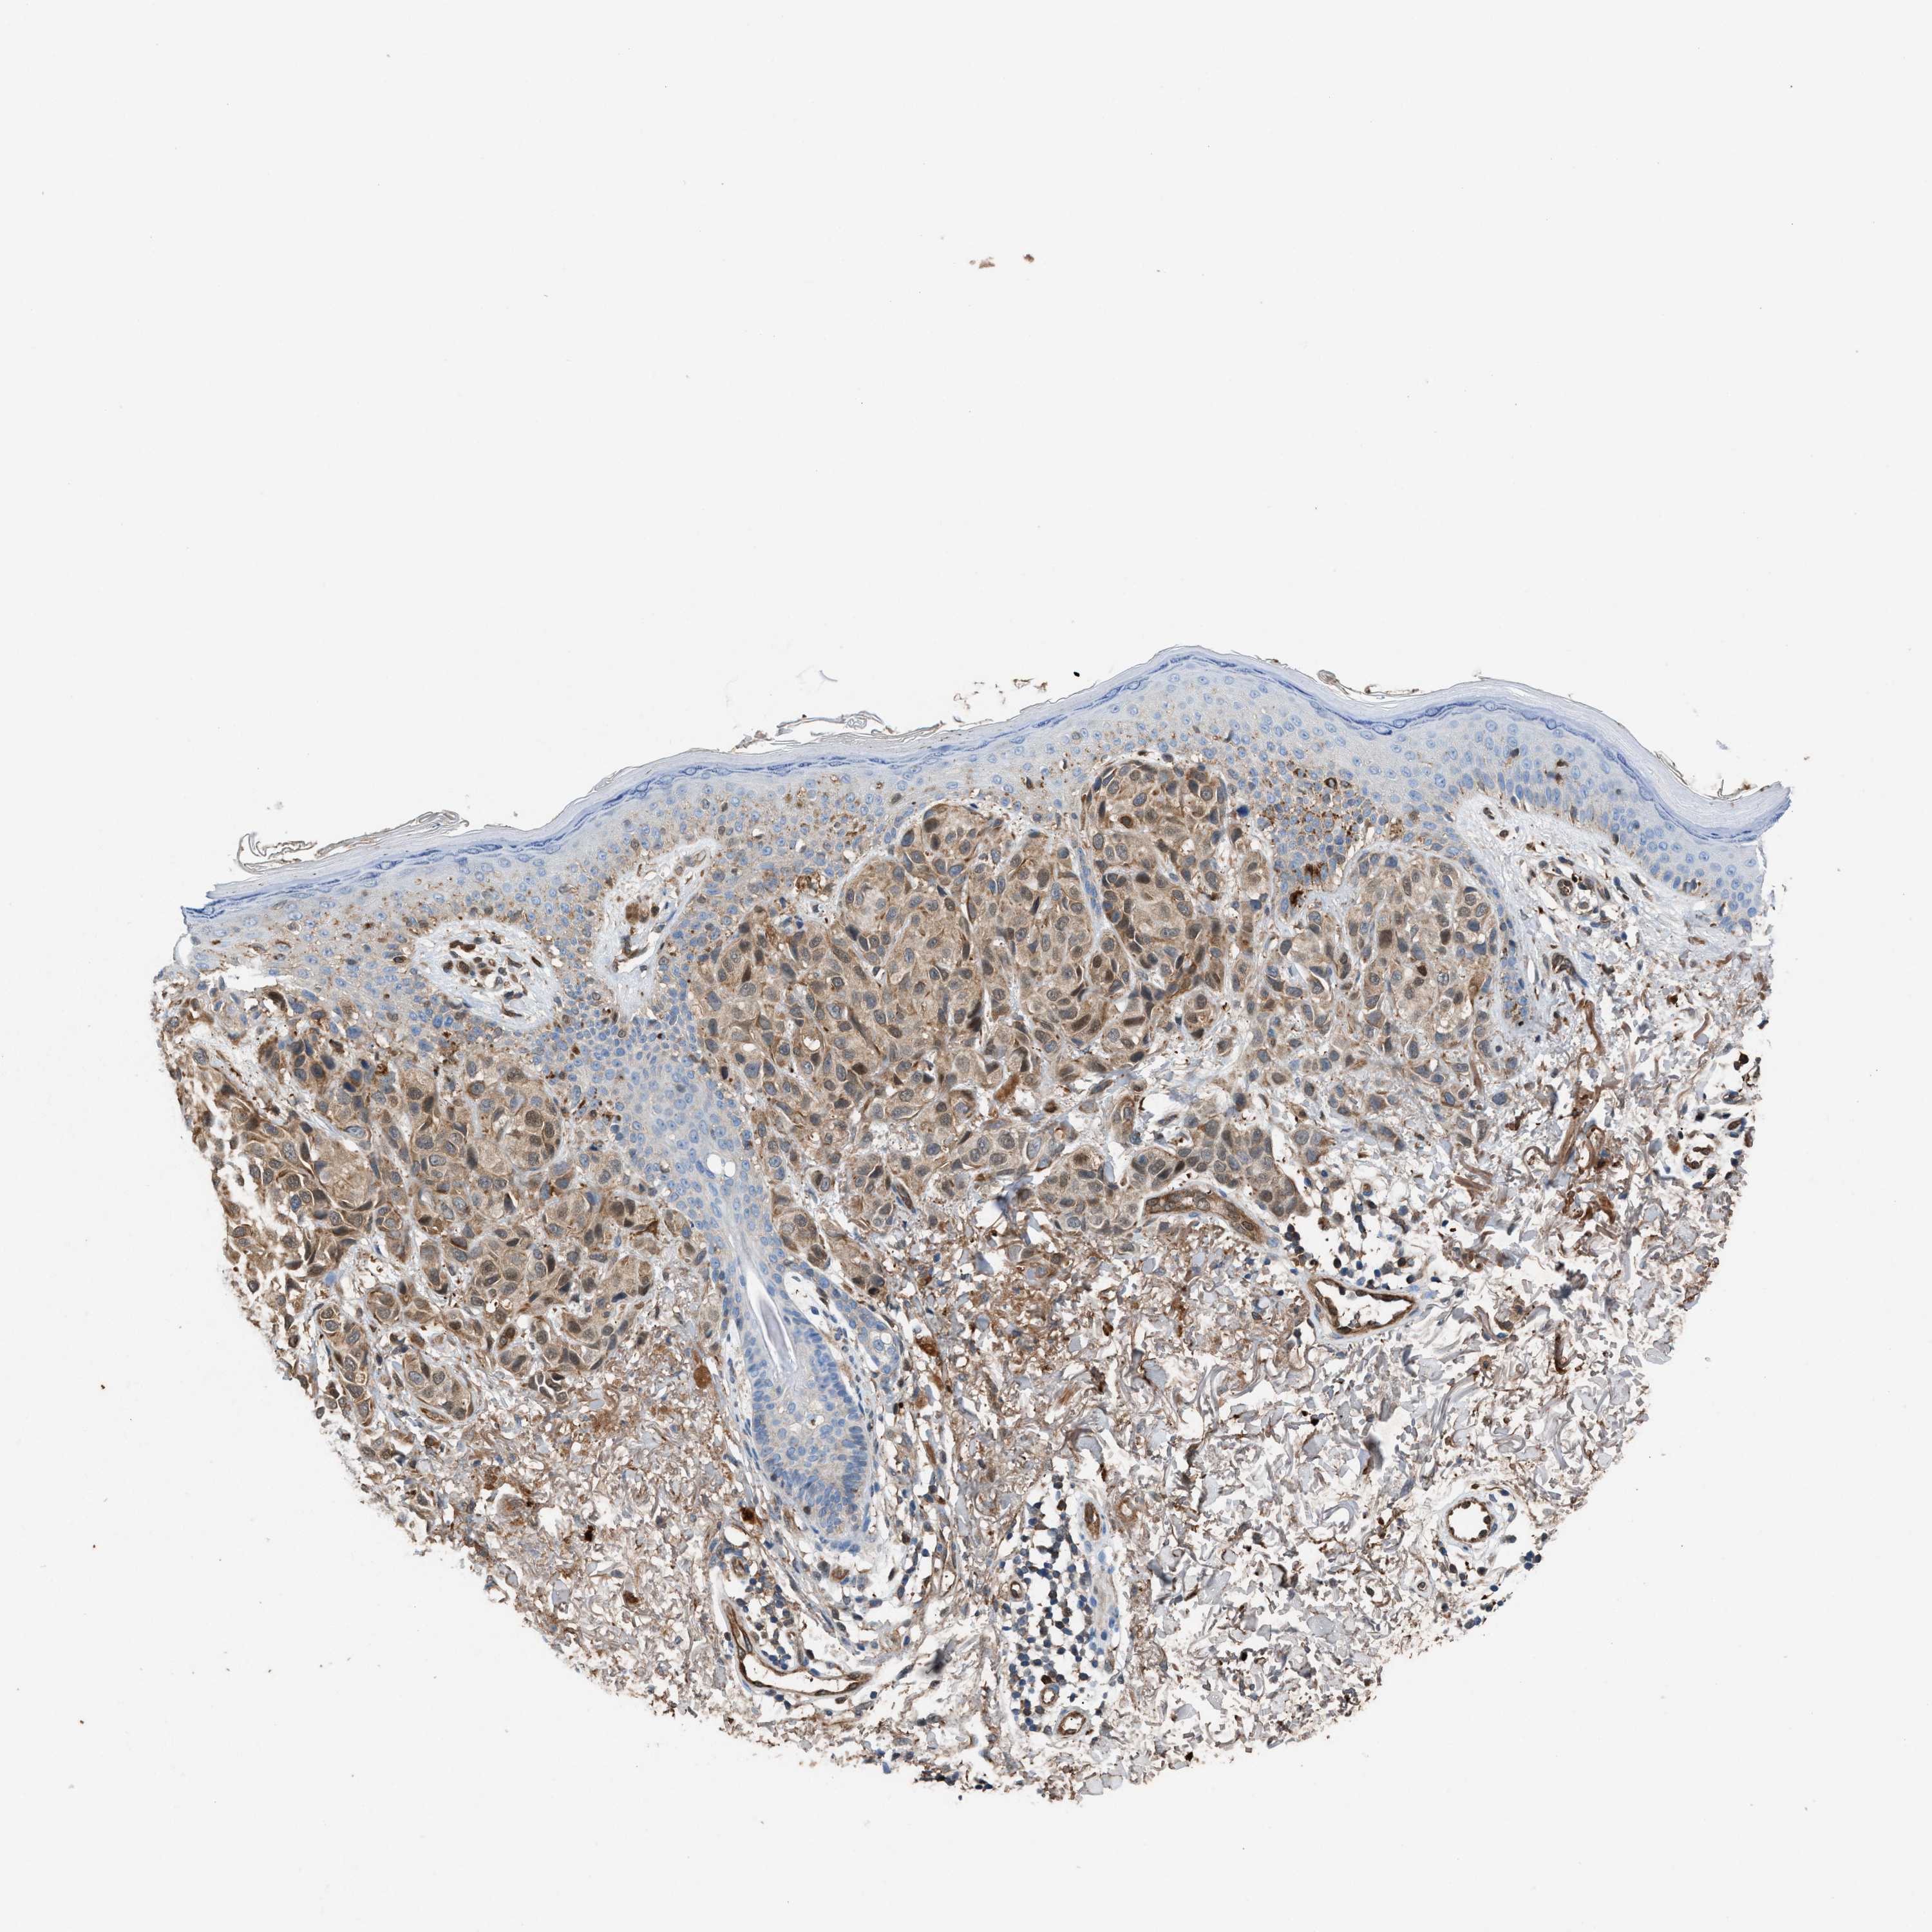

MELANOMA - Protein expressioni

A mouse-over function shows sample information and annotation data. Click on an image to view it in a full screen mode. Samples can be filtered based on level of antibody staining by selecting one or several of the following categories: high, medium, low and not detected. The assay and annotation is described here.

Note that samples used for immunohistochemistry by the Human Protein Atlas do not correspond to samples in the TCGA dataset.

Antibody stainingi

Antibody staining in the annotated cell types in the current human tissue is reported as not detected, low, medium, or high, based on conventional immunohistochemistry profiling in selected tissues. This score is based on the combination of the staining intensity and fraction of stained cells.

Each image is clickable and will lead to virtual microscopy that enables deeper exploration of all samples and also displays staining intensity scores, fraction scores and subcellular localization as well as patient and tissue information for each sample.

Antibody HPA021545

Antibody HPA021849

Staining

High

Medium

Low

Not detected

Intensity

Strong

Moderate

Weak

Negative

Quantity

>75%

75%-25%

<25%

None

Location

Nuclear

Cytoplasmic/membranous

Cytoplasmic/membranous,nuclear

Malignant melanoma, NOS

Malignant melanoma, Metastatic site